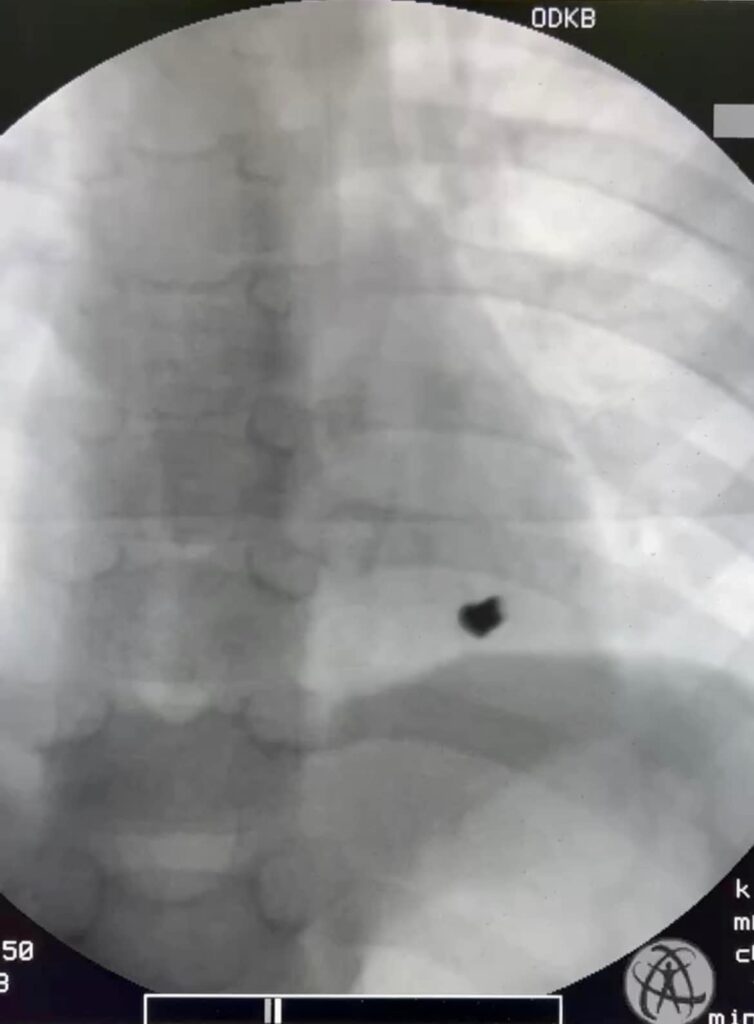

Двоє хлопчиків семи та восьми років гралися з гвинтівкою, що виявилася зарядженою. В результаті семирічна дитина отримала поранення лівої частини грудної стінки. Куля проникла в серце та уразила лівий шлуночок.